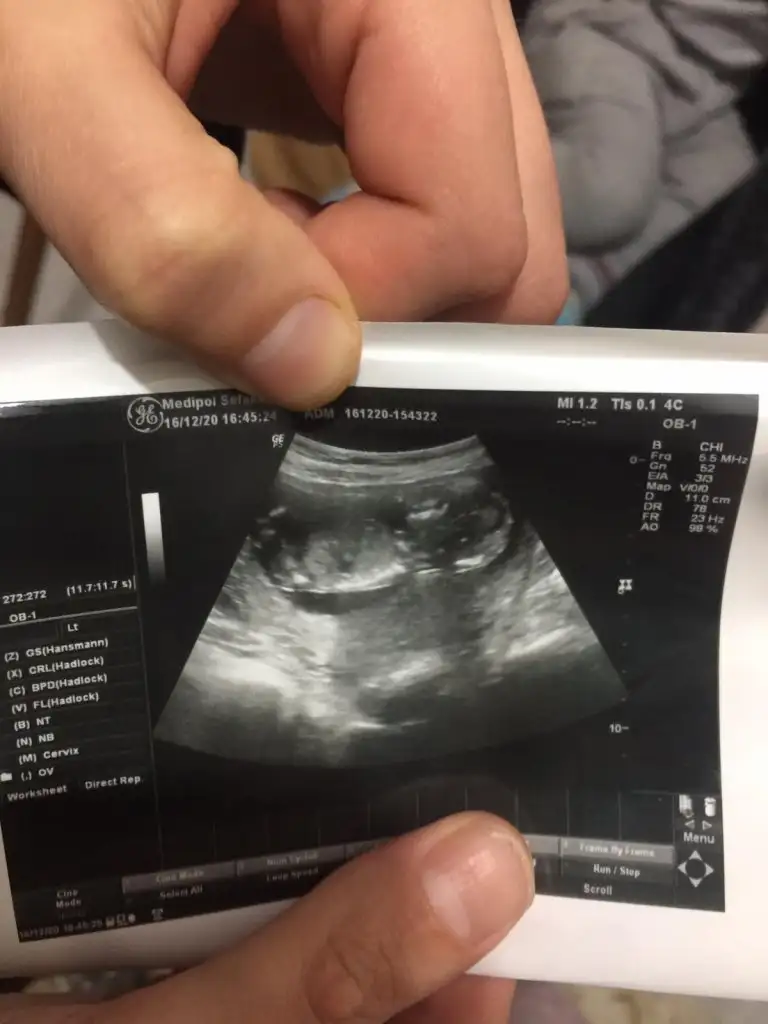

Seninkini at bakayım birde ben göreyim 🤭 ben aslında 12. Haftada gittiğimde kız olduğunu fark ettim pipi gibi birşey yoktu assagi doğru eyik gözükuyordu🤗

Bizimkide bu su pipi mi kordon mu anlamadım 😅 insallah kordondur yeni oluşan pipi bu kadar büyük olur mu acaba 😅

Eklentiler

• IMG-20201216-WA0003.webp

IMG-20201216-WA0003.webp

25,9 KB · Görüntüleme: 62